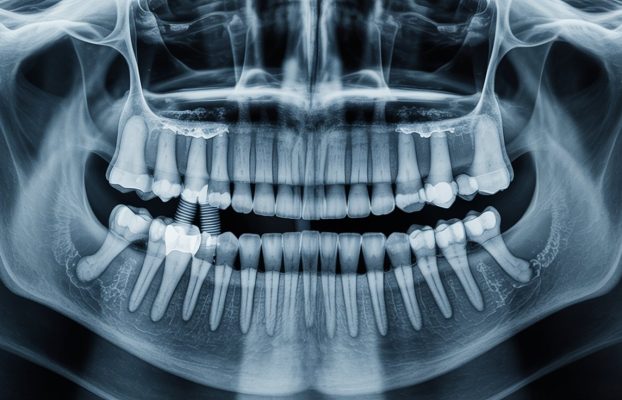

Zygoma implants offer durable and reliable implant solutions placed in the cheekbones for patients with jaw bone deficiency. It is an ideal treatment option for a healthy and aesthetic smile.

Zygoma implant is also known as cheekbone implant. There is general information about the zygoma implant, which is the most effective treatment method for patients who have permanently lost their teeth. The curious details about the increasingly popular treatment are as follows: